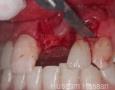

Surgery